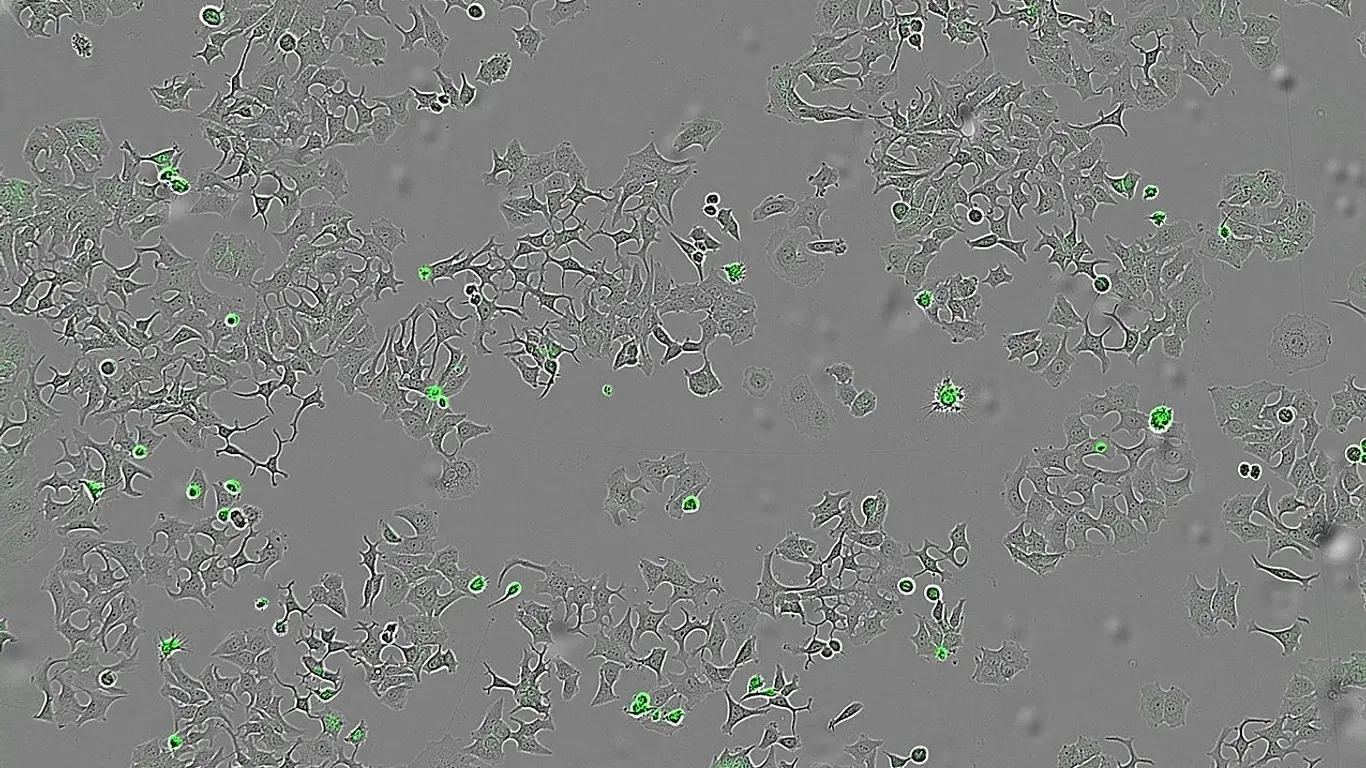

Bilim insanları, bu proteinin meme, kalın bağırsak ve pankreas kanseri hücreleri üzerinde etkili olduğunu belirledi. HapA, tümör hücrelerinin yüzeyinde bulunan PAR-1 ve PAR-2 reseptörlerine bağlanarak bu reseptörleri insan enzimlerinden farklı bir noktadan kesiyor ve hücreyi intihara sürüklüyor.

Deneylerde sonuç net: HapA proteini bulunan ortamlarda tümör hücreleri yok olurken, bu proteini üretmeyen bakterilerin bulunduğu ortamlarda hücrelerin yaşamaya devam ettiği gözlemlendi.